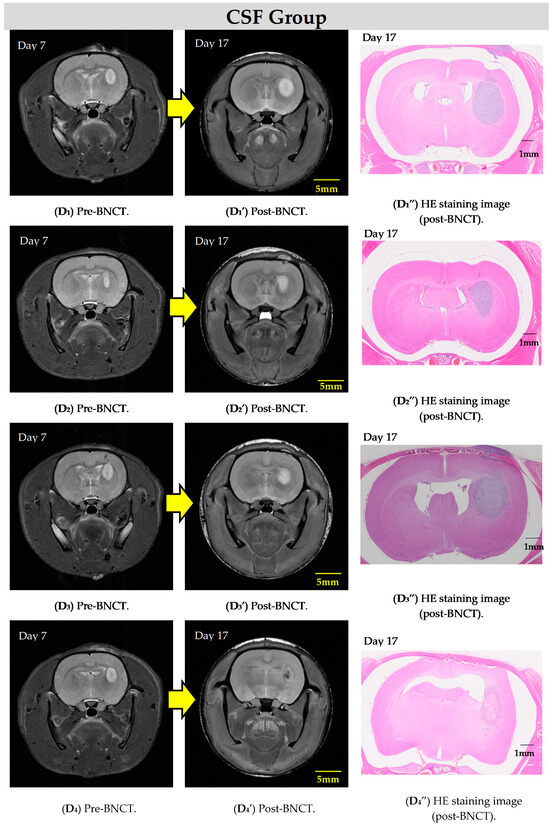

The MR images for each group are depicted in Figure 3. Compared to the control groups, inhibition of tumor growth is observed in the groups administered BPA (via both IV and CSF).

Figure 3.

The T2WIs show representative examples of rat heads before and after BNCT in each group. It can be observed that increases in tumor size are suppressed in the IV (C,C′,C″) and CSF (D1–D4,D1′–D4′,D1″–D4″) groups compared to the control groups (cold (A,A′,A″) and hot (B,B′,B″)).

In the present study, some rats exhibit not only inhibited tumor growth but also a significant reduction in tumor volume as early as one week after BNCT with the IV BPA administration, highlighting the notable effectiveness of this therapy in rat models. Figure 4 demonstrates the remarkable histologically normal tissue levels post-treatment. When comparing the two administration methods, based on pathological examination, the IV method with a BPA dose of 350 mg/kg demonstrates better performance over the CSF method with a dose of 8 mg/kg/h (total 16 mg/kg), albeit only slightly.